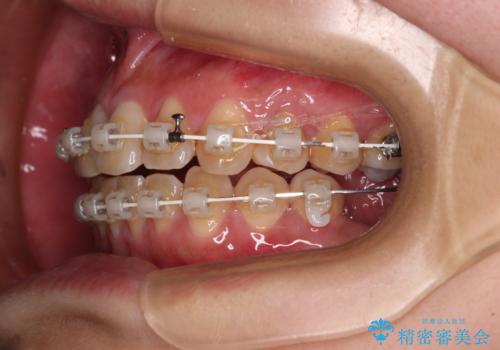

- 奥歯に問題が多くて困っているとのことで来院された患者様です。

開咬により奥歯のみが接触している状態で、前歯部にほとんど接触のない状態で、奥歯に非常に負担のかかる咬み合わせでした。

また、欠損や根管治療の必要な歯など、むし歯による問題も多く散見されました。

まずはむし歯の治療を行い、その後ワイヤー矯正にて咬み合わせを改善し、途中インプラント埋入を行い、矯正治療後に補綴治療を行うこととしました。